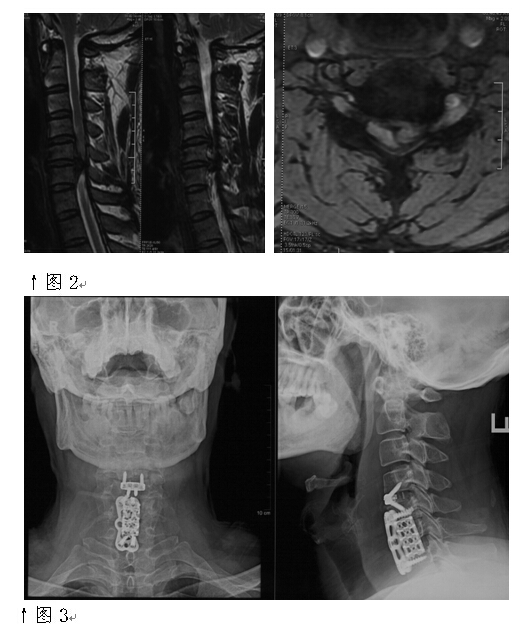

2015年底。空军总医院由黄美良副院长率领的医疗队赴满洲里“踏雪送健康”义诊。前来就诊的44岁男性患者郑某,半年前出现四肢麻木,走路不稳,感觉像踩棉花似的,就诊时已无法独立行走。黄副院长征得本人及家属同意后,决定将他带到医院接受手术治疗。杜主任接诊后认真询问了患者发病史,并结合该患者影像资料,针对确诊的 “颈椎间盘突出症伴不全瘫”制定手术方案。由于患者颈4-5,颈5-6椎间盘突出巨大,且颈5-6突出的椎间盘组织掉入椎管内游离并占据了整个颈6椎体后缘(见图2),表明该手术的难度和风险也一并倍增。

凭借所掌握的过硬技术,以杜主任为首的医疗团队当即决定,为该患者实施“颈椎前路C4-5椎间盘切除减压、C6椎体次全切、植骨融合内固定”手术。术中仅凭一个5公分切口便解除了患者2个节段椎间盘巨大突出及椎管狭窄,以及三个节段的颈椎融合问题(见图3)。手术独具匠心,术后患者颈部不适症状消失,3天后可以行走。